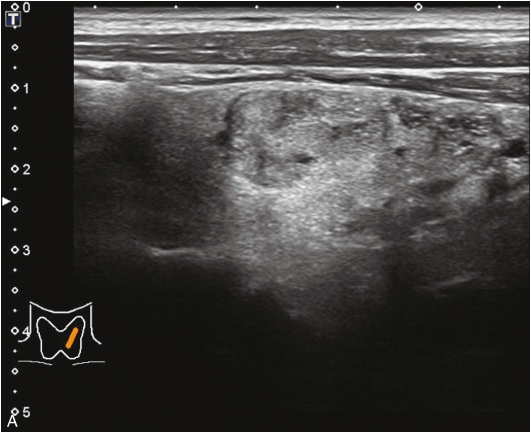

甲状腺左叶明显增大,可见一囊性为主的囊实性结节,该结节体积较2年前明显增大,挤压周围甲状腺组织,结节内部回声欠均匀,见多发点、条状强回声,结节后方回声增强;CDFI显示结节内部未见明显血流信号,见图1-3-3。

图1-3-3 甲状腺囊肿伴出血常规超声声像图

A.甲状腺左叶横切面;B.CDFI血流图